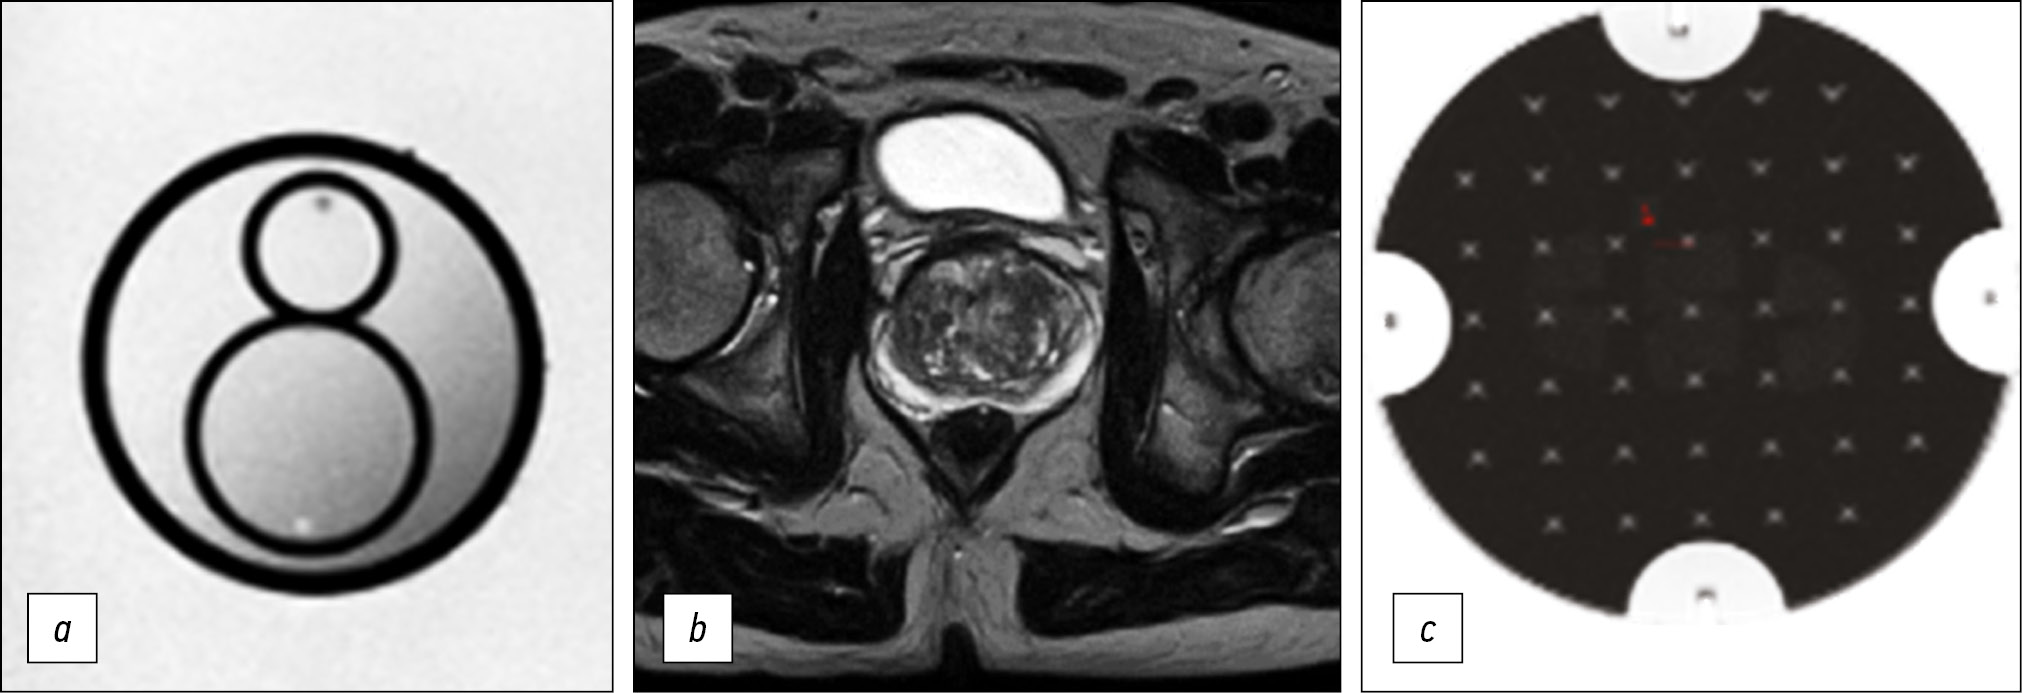

材料与方法。莫斯科市卫生管理局医疗机构对获得的前列腺磁共振图像进行的初步分析表明,该研究的实施缺乏统一的方法。通过反复调整扫描参数,我们建立了一个协议,可提供可接受的可视化质量,同时尽可能满足PI-RADS要求。为了量化所获得图像的质量,使用了美国放射科医师协会推荐的磁共振成像控制体模。

结果。我们已为Excelart Vantage1.5 T断层扫描仪开发了一个优化的双参数协议,其中包括三个平面的作加权像和弥散加权成像 ,总时间不到11分钟。同时,确保了高水平的前列腺细节,图像质量参数(亮度不均匀性、非线性、分辨率和所选部分的厚度)对应于制造商的可接受范围。